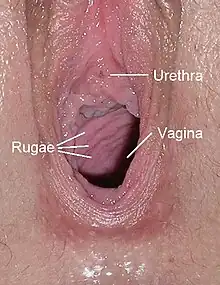

Human vagina; normal canal (left) and canal during menopause (right) | |

The human vagina is an elastic, muscular canal that extends from the vulva to the cervix.[9][10] The opening of the vagina lies in the urogenital triangle. The urogenital triangle is the front triangle of the perineum and also consists of the urethral opening and associated parts of the external genitalia.[11] The vaginal canal travels upwards and backwards, between the urethra at the front, and the rectum at the back. Near the upper vagina, the cervix protrudes into the vagina on its front surface at approximately a 90 degree angle.[12] The vaginal and urethral openings are protected by the labia.[13]

Vaginal opening and hymen

The vaginal opening (also known as the vaginal introitus)[20] is at the posterior end of the vulval vestibule, behind the urethral opening. The opening to the vagina is normally obscured by the labia minora (inner lips), but may be exposed after vaginal delivery.[10]